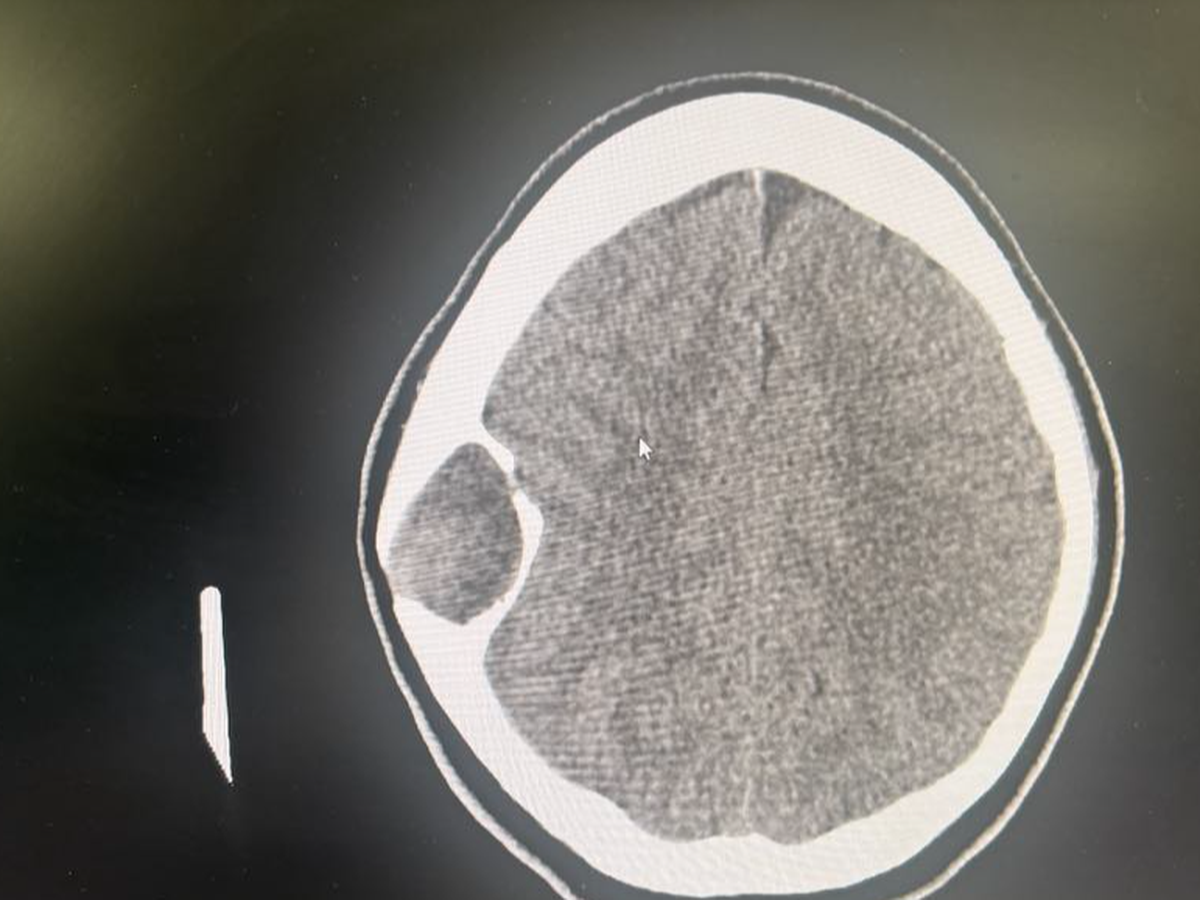

Since January, she’s been battling nonstop headaches, dizziness, and blurry vision. She’s been in and out of doctor’s offices and hospitals with no real answers—just a lot of waiting rooms, medical bills, and frustration.

A few days ago, things got worse, and she went to the ER. They did a CT scan and told her they’d refer her to a neurosurgeon… eventually. But Kaylee wasn’t about to sit around and wait while her head was pounding. So she marched herself straight to OSU. Within an hour, they admitted her to The James Cancer Hospital.

They did an MRI and two doctors came in to tell her:

It’s a benign bone tumor in her skull bone—something she was born with—and it CAN be removed.